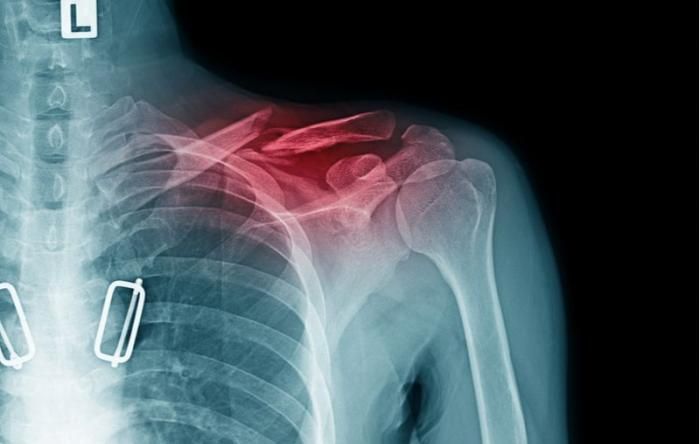

A clavicle fracture is a break or discontinuity in the collarbone, which connects the sternum (breastbone) to the scapula (shoulder blade). It commonly occurs in the middle third of the bone.

- Pain and tenderness over the clavicle

- Visible deformity or “step” sign

- Restricted shoulder movement

- Swelling and redness